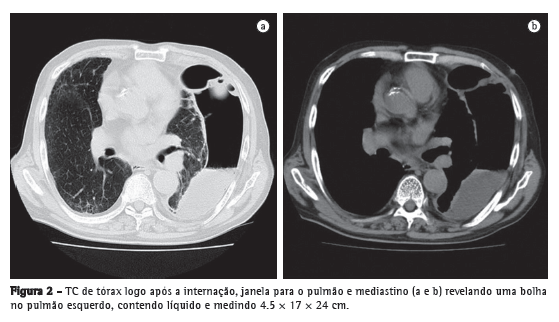

Um homem de 79 anos de idade buscou tratamento no pronto-socorro devido a um histórico de 3 meses de febre persistente, dor torácica e fadiga geral. Apresentava carga tabágica de 60 anos-maço e fizera uso pesado de saquê japonês (180 mL/dia) durante os últimos trinta anos. Os exames laboratoriais realizados indicaram a presença de inflamação grave, e a radiografia de tórax revelou uma bolha gigante de 24 cm de diâmetro no pulmão esquerdo (Figura 1a). Segundo o próprio paciente, não apresentava histórico de alterações radiográficas, e seu último check-up médico, realizado no ano anterior, não revelara anormalidades (Figura 1b). A TC de tórax revelou que a bolha continha líquido e media 4.5 × 17 × 24 cm (Figura 2). O paciente foi diagnosticado com abscesso pulmonar e foi internado em nosso hospital.